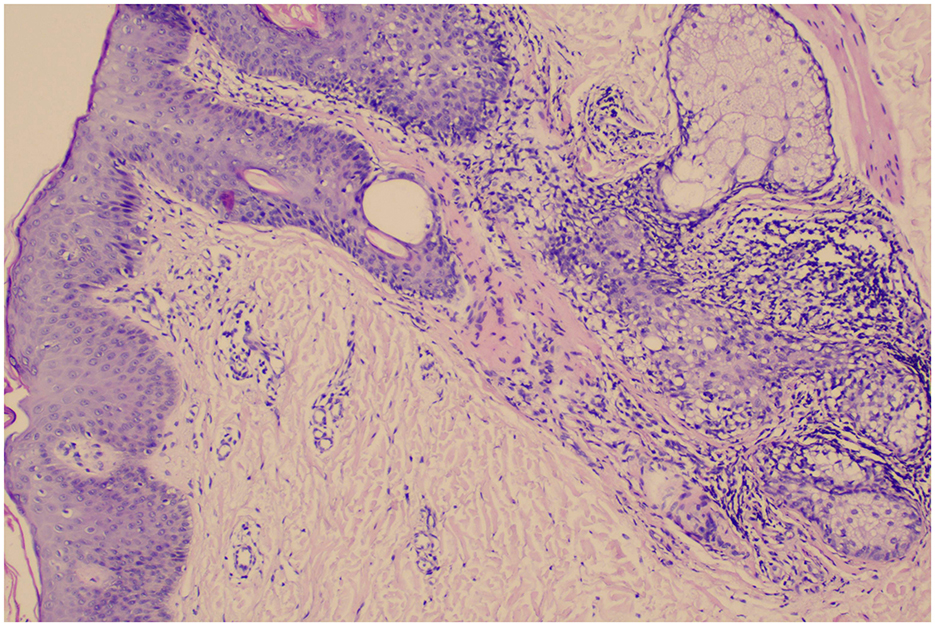

Histopathological examination

Biopsy of the skin lesions showed epidermal hyperkeratosis with parakeratosis, neutrophil aggregates, and hypertrophy of the stratum spinosum; elongation of dermal papillae, capillary dilatation, and perivascular infiltration by lymphocytes and neutrophils (Figure 4).

Figure 4. Biopsy of the skin lesions showed epidermal hyperkeratosis with parakeratosis, neutrophil aggregates, and hypertrophy of the stratum spinosum; elongation of dermal papillae, capillary dilatation, and perivascular infiltration by lymphocytes and neutrophils.